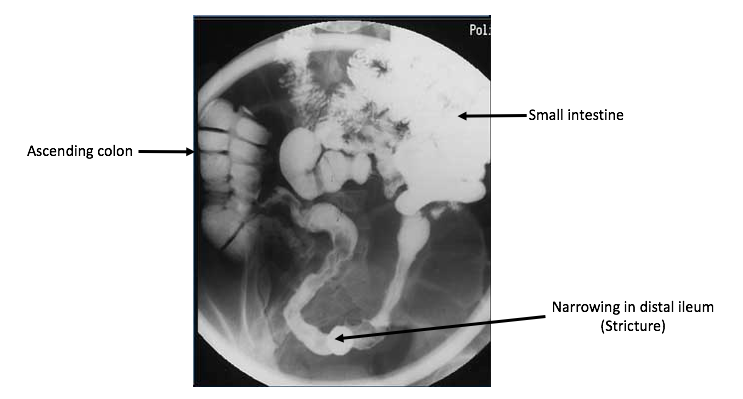

Colicky pain= wave like pain that has mild pain and then bouts of severe pain (non specific)

X-ray shows air-fluid levels (Caused by distension)

Could be CD, or something is obstructing the abdomen